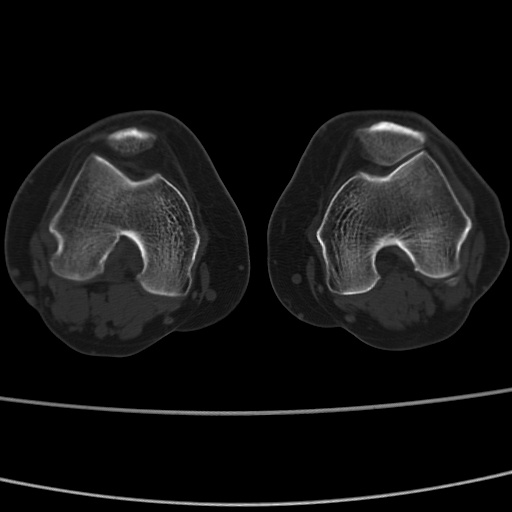

女性,50岁。【请提供患者临床症状体征】

右膝关节退行性改变,关节游离鼠。

右膝关节退行性改变,滑膜黏液囊钙/骨化并游离。

右膝关节退行性改变